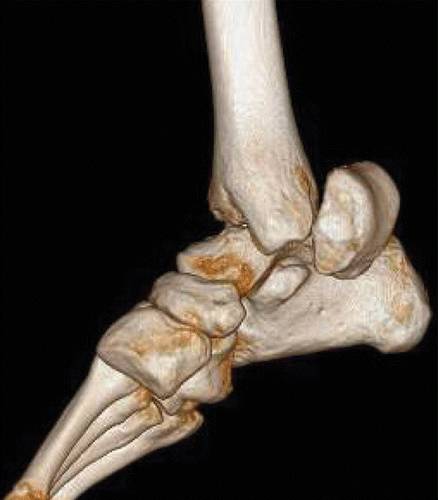

图1a距骨的正常解剖。 三维重建计算断层(CT)图像显示在上(a)和下(b)投影中的距骨及其关键部件。